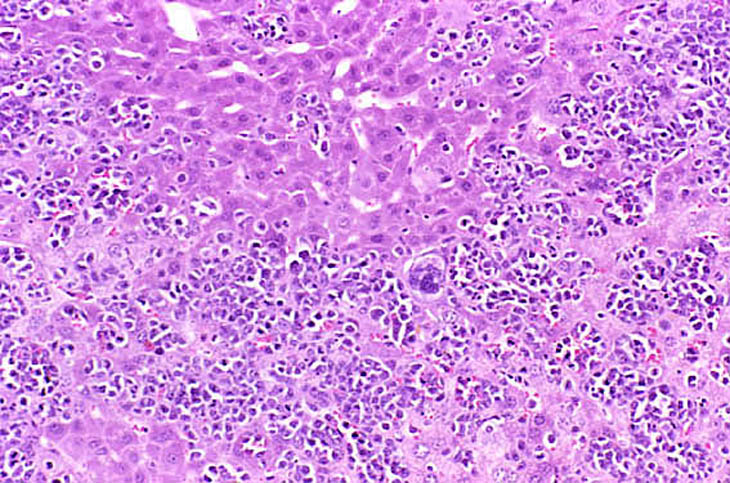

The liver is a relatively frequent site of infiltration by malignant lymphocytes, especially in strains with a high prevalence of lymphoma.

Infiltration of malignant lymphocytes in a liver from an adult mouse.

Severe infiltration of the liver by malignant lymphocytes. Hepatocytes visible in the lower right corner.